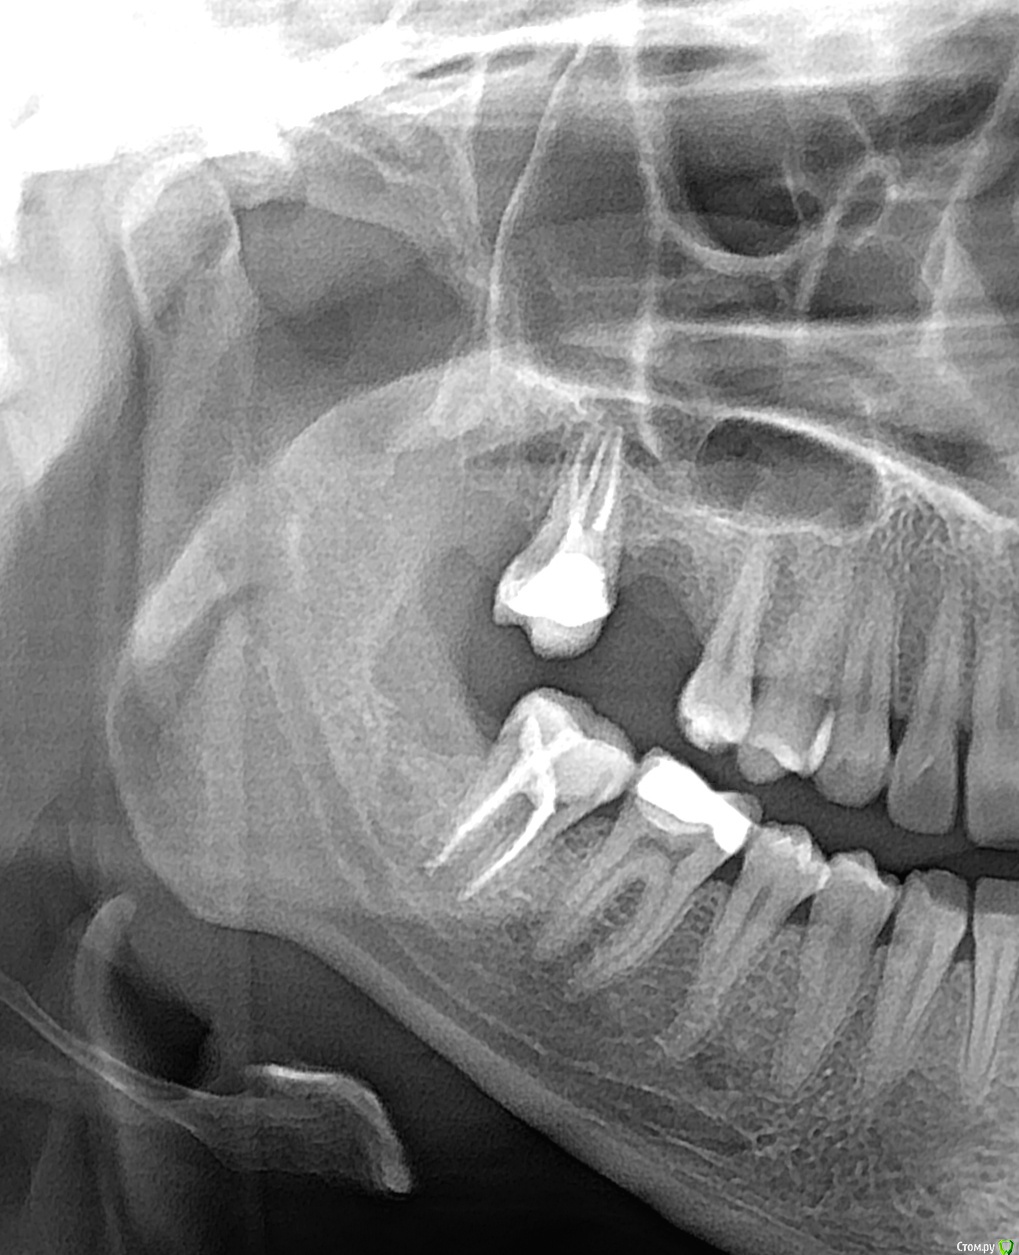

Аннушккка Опубликовано 27 марта, 2020 Поделиться Опубликовано 27 марта, 2020 (изменено) Болит верхняя 7ка и нижняя 7 ка и 5 ка что это врачи не видят ничего плохого Изменено 27 марта, 2020 пользователем Аннушккка Ссылка на комментарий

red_butler Опубликовано 28 марта, 2020 Поделиться Опубликовано 28 марта, 2020 Я бы проверил 4.6 зуб на предмет пульпита 1 Ссылка на комментарий

Аннушккка Опубликовано 2 апреля, 2020 Автор Поделиться Опубликовано 2 апреля, 2020 Ходила в больницу говорят что нужно к ортодонту т.к может пиикус, но на корне у 7 нижнего зуба говорят ккк немного материал выведен,; он как раз при постукивании очень болит, шестой нижний не реагирует ни на что, но самое смешное что 5 зуб его буд то распирает, десна возле него кровит, и когда на него языком надовить легче, а так он постоянно болит, прям кашмар, но визуально он в отличном состоянии, и врачи говорят чтт смысла нет его раскрывать удалять нерв.но его своди просто я не знаю уже что делать, если на него наложить ватный диск и зажать зубами становится немного легче Ссылка на комментарий